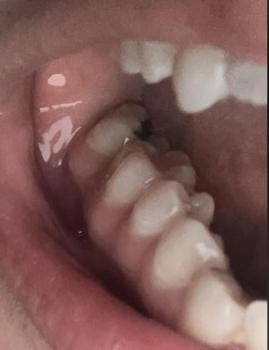

The dental X-ray shows bone changes around the roots of the teeth, particularly in the back tooth area. There are visible signs of bone loss and darkened areas near the root tips, which commonly indicate a tooth abscess or chronic dental infection.

Some teeth appear previously treated, but the surrounding bone suggests ongoing or unresolved infection.

This X-ray shows bone infection around tooth roots, often without obvious pain at first. Early dental intervention is critical to preserve bone, prevent abscess spread, and protect overall oral health.